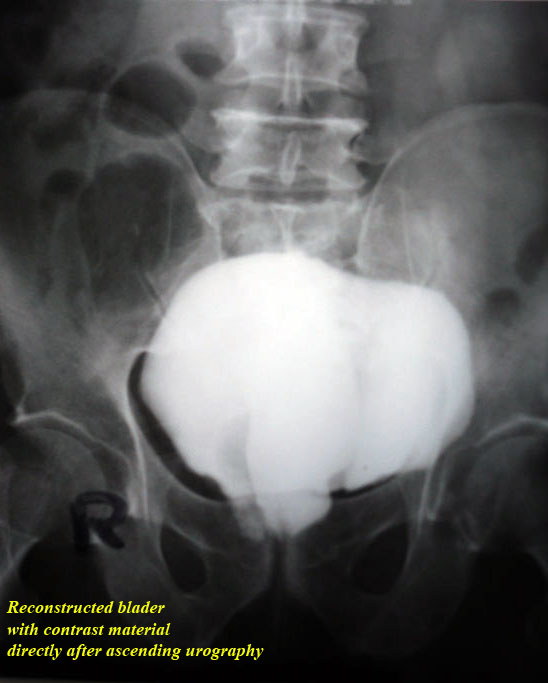

treatment. By difficulty we persuaded him to do ascending urography

" see photos".

Do you think that these photos were

convincing for the patient?

In order to satisfy him by this

diagnosis we advised him to defecate after the ascending urography,

as he saw by his own eyes the dye passing instead of stool, he

accepted !!